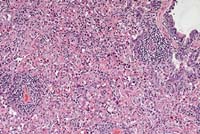

Case 9-1. Skin. Well-differentiated eosinophils clustered in a dilated venule and infiltrating the dermis. 40X

AFIP Diagnosis: Haired skin, dermis and subcutis: Eosinophil infiltrate, severe, with fibrosis and fewer lymphocytes, plasma cells, mast cells and neutrophils, New Zealand white rabbit, lagomorph.

Conference Note: Although the contributor's diagnosis was carefully considered, and it is agreed that the submitted case resembles that reported by Perkins et al., it was concluded that the nature of the process represented in the skin sections is uncertain. Since the infiltrate does not contain atypical cells, blasts or immature myeloid cells, a reactive lesion cannot be excluded. Possible causes include hypersensitivity, parasites, drugs and non-eosinophil neoplasia.